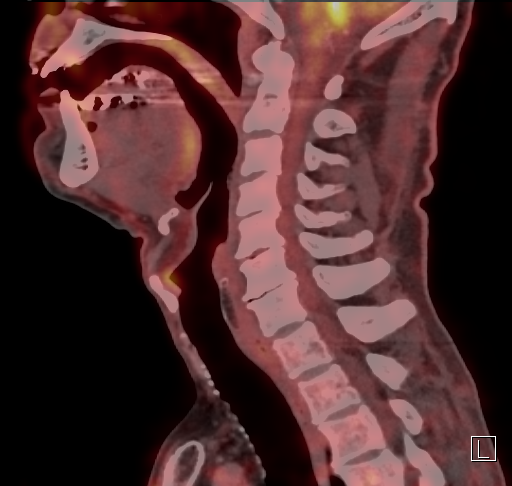

De stembandkanker, van het plaveiselcel type zoals bleek uit de biopsie, had

ik zelf al opgemerkt door enkele symptomatische veranderingen in mijn eigen

stemgeluid. Ik kon het ook zelf zien op de beelden van de laryngoscopie in het

ziekenhuis. De kwaadaardigheid kon worden bevestigd door een PET-scan: